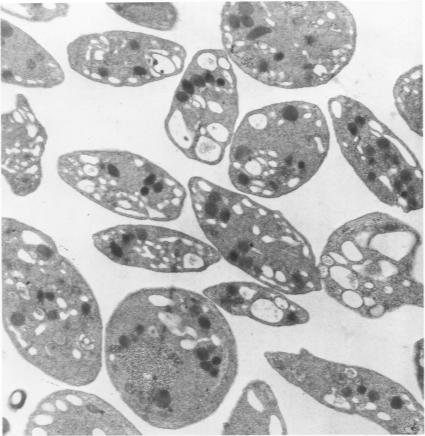

The mechanisms of urate-crystal-induced release of platelet constituents has been studied morphologically and biochemically. Urate crystals provoked an early energy-dependent release of the dense-body constituents serotonin, ADP, and ATP from washed platelets. Concurrently, platelet ultrastructure showed evidence of shape change, contractile wave, and aggregation. These are typical morphologic concomitants of platelet secretion. By 30 minutes' incubation, urate-induced platelet lysis occurred, as shown by loss of the cytoplasmic enzyme lactic dehydrogenase (LDH) and ultrastructurally by disruption of platelet membrane integrity. Cytochalasin B inhibited the urate-crystal-induced shape change, aggregation, and disruption of cell membranes. Platelet degranulation was not inhibited and the initial component of serotonin release was not affected. Cytochalasin B also abrogated crystal-induced LDH loss. Thus, the initial crystal-induced serotonin release does not depend on platelet lysis. It is concluded that urate-crystal--induced release of serotonin, ATP, and ADP represents an example of platelet secretion.

已从形态学和生物化学方面对尿酸盐晶体诱导血小板成分释放的机制进行了研究。尿酸盐晶体促使洗涤后的血小板早期以能量依赖方式释放致密体成分5-羟色胺、二磷酸腺苷(ADP)和三磷酸腺苷(ATP)。同时,血小板超微结构显示出形状改变、收缩波和聚集的迹象。这些是血小板分泌的典型形态学伴随现象。孵育30分钟后,出现尿酸盐诱导的血小板溶解,表现为细胞质酶乳酸脱氢酶(LDH)丧失,超微结构显示血小板膜完整性遭到破坏。细胞松弛素B抑制尿酸盐晶体诱导的形状改变、聚集以及细胞膜破坏。血小板脱颗粒未受抑制,5-羟色胺释放的初始成分未受影响。细胞松弛素B也消除了晶体诱导的LDH丧失。因此,最初晶体诱导的5-羟色胺释放不依赖于血小板溶解。得出的结论是,尿酸盐晶体诱导的5-羟色胺、ATP和ADP释放是血小板分泌的一个实例。